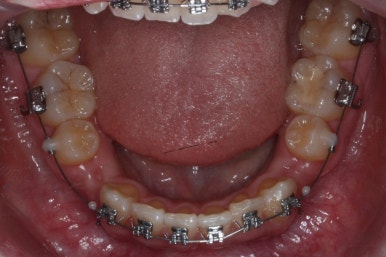

이제 치료가 끝났습니다.

매우 치아가 가지런해졌고, 당연히 덧니는 해소가 되었으며 맞물림도 굉장히 좋아졌습니다.

다른 분드로가의 차이점은 치료 종료 후 유지장치를 할 때 앞니만 하는 것이 아니라 발치한 자리가 다시 벌어지지 말라고 약간 연장해서 유지장치를 부착해 주게 됩니다.

치아가 매우 가지런해졌고, 덧니도 개선이 되었습니다.

맞물림도 굉장히 좋아졌네요.